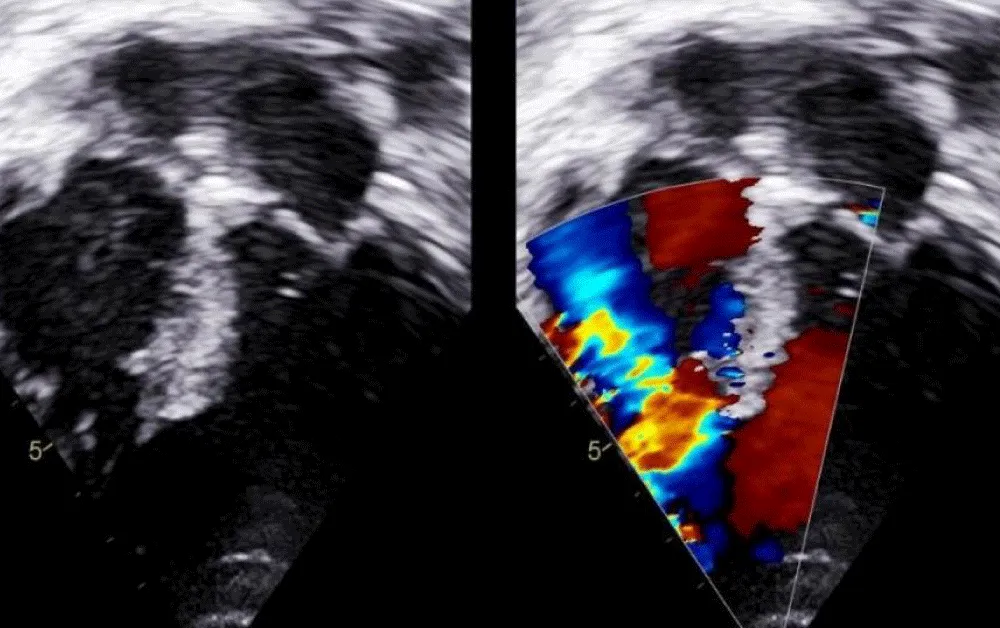

There was no use of transesophageal echocardiography due to the unavailability of a suitable probe. Left Ventricular angiogram was done to determine the exact location of the VSR (Figure 2). Cannulation of the right femoral artery and right internal jugular vein or right femoral vein was performed using the Seldinger technique. A guidewire (03500 Terumo guidewire) was introduced from the femoral artery, through the aorta into the left ventricle, and advanced through the VSR into the right ventricle and pulmonary artery. A second snaring wire was introduced through the vein (Either jugular or femoral) to connect to the guidewire in the pulmonary artery. By retracting the snared wires, the guidewire now forms an arteriovenous (AV) loop. The delivery sheath was advanced from the venous side loop over the guidewire through the VSR into the left ventricle. Correct positioning of the delivery sheath is confirmed in fluoroscopy/TTE. The guidewire is then retracted leaving the delivery sheath in position. After the echocardiographic confirmation occluder device was deployed across VSR using the delivery sheath (Figure 3). Correct positioning of the device and closure was confirmed by transthoracic echocardiography and/or fluoroscopy. If placement is satisfactory, the occluder is released. Post-procedure Left ventricular angiography and transthoracic echocardiography (Figure 4) were done to confirm the position and to rule out the presence of any residual shunt. We did not perform transoesophageal echocardiography for delineation of post-MI VSR, in any of the patients of our series due to the lack of availability of probes. In two cases we did not use any contrast agent (angiography) to delineate VSR because both patients had very high levels of urea and creatinine. Out of 11, in 10 cases, we made use of the femoral-jugular mode of access and created an AV loop. In one case we made a femoral arterio-venous loop. The veno-venous loop though described in literature was not used in this study.

Figure 4: Transthoracic echocardiography done to confirm the position and to rule out the presence of any residual shunt.